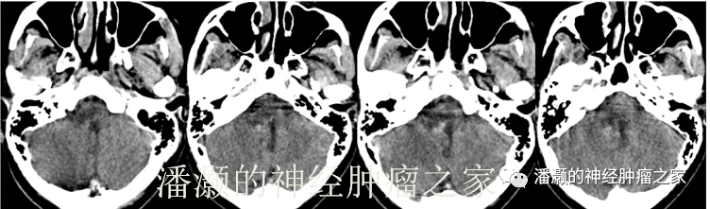

2018.9.28术后CT:

手术后患者同术前一样,仍有饮水呛咳,声音嘶哑,自主呼吸良好。考虑短期内很难完全恢复,所以给予气管切开。出院前一般状况良好,KPS60分,鼻饲饮食,肢体肌力正常。